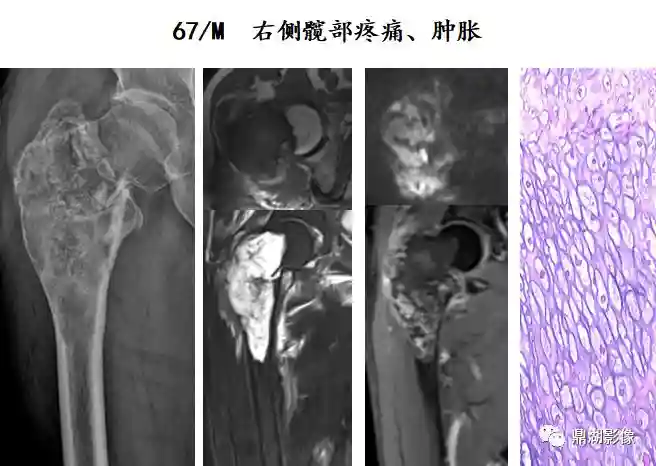

软骨肉瘤

起源于软骨或成软骨结缔组织肿瘤,约占骨恶性肿瘤20%

发病年龄多40-70岁,男多于女,长骨及骨盆多见

溶骨性骨质破坏,边界不清,软组织肿块

病灶内可见数量不等、分布不均、疏密不一的钙化

偶见骨膜反应和Codman三角